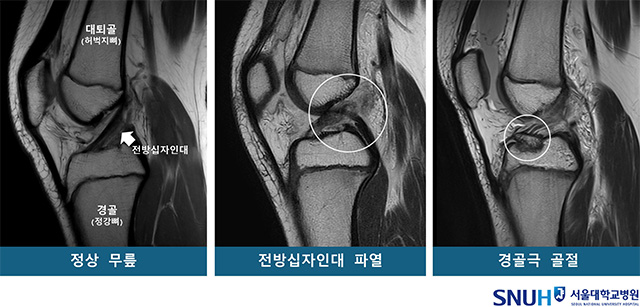

연구팀은 환자군을 ▲전방십자인대 파열군(53명) ▲경골극 골절군(53명) ▲정상군(대조군, 53명)으로 나눈 뒤, 무릎 MRI 영상에서 14개의 해부학 지표를 측정했다. 분석 결과, 경골 바깥쪽 관절면의 경사가 가파를수록 전방십자인대 파열(ACL rupture)과 경골극 골절(트리플 플레이트 avulsion fracture)의 위험이 각각 1.42배, 1.33배 높아졌다.

또한 대퇴과간 절흔 폭, 즉 무릎뼈 사이 공간이 좁을수록 전방십자인대 파열 위험이 커지지만, 이 공간이 넓을 경우 보호 효과가 나타났다. 연구진은 “관절면 경사가 클수록 대퇴골이 바깥쪽으로 회전하며 무릎 전방십자인대에 과부하를 유발하고, 절흔 폭이 좁을 경우 인대가 더 많이 충돌한다는 점에서 해부학적 구조가 손상 기전에 영향을 준다”고 설명했다.